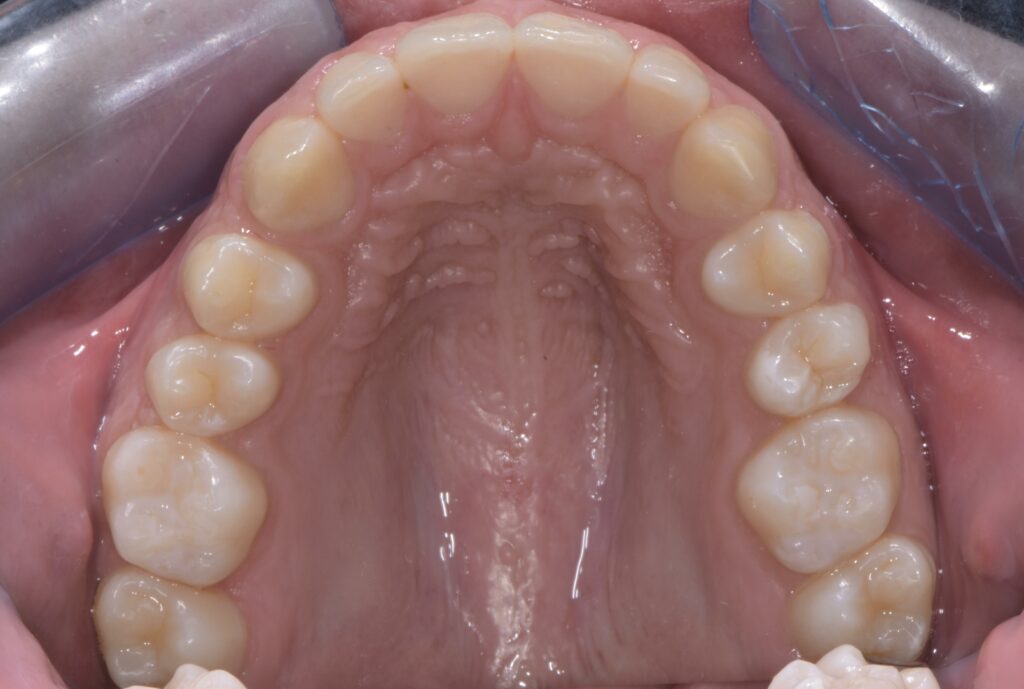

Dopo la sigillatura:

- Solchi e fossette perfettamente protetti da una resina trasparente.

- Riduzione significativa del rischio di carie grazie alla barriera protettiva che impedisce l’ingresso di batteri e residui alimentari.